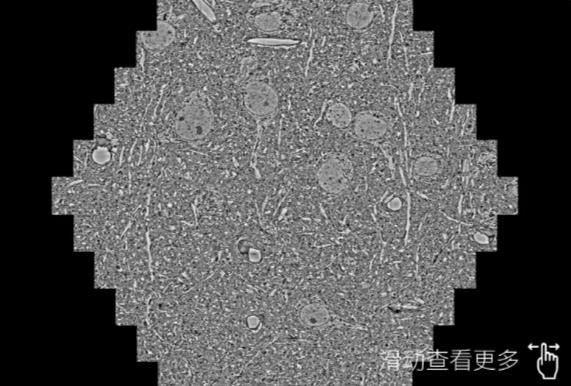

鼠脑切片。左图使用丰满蔡司丰满扫描电镜MultiSEM706对165μmx143pm面积区域成像,耗时仅需1.5秒。右图为鼠脑切片中30μm区域放大效果。样品由芝加哥大学B.Kasthuri提供。